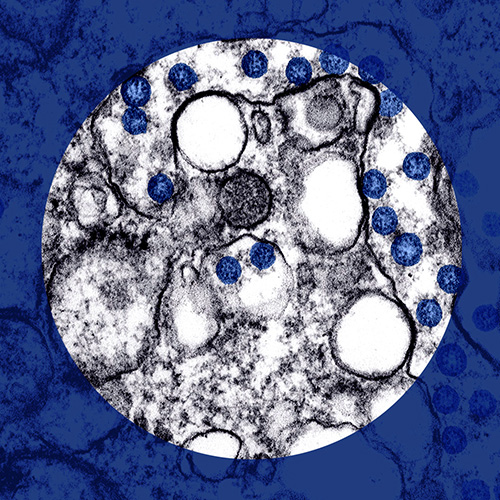

The long-term health effects of Covid-19 may put more pressure on the pharma industry